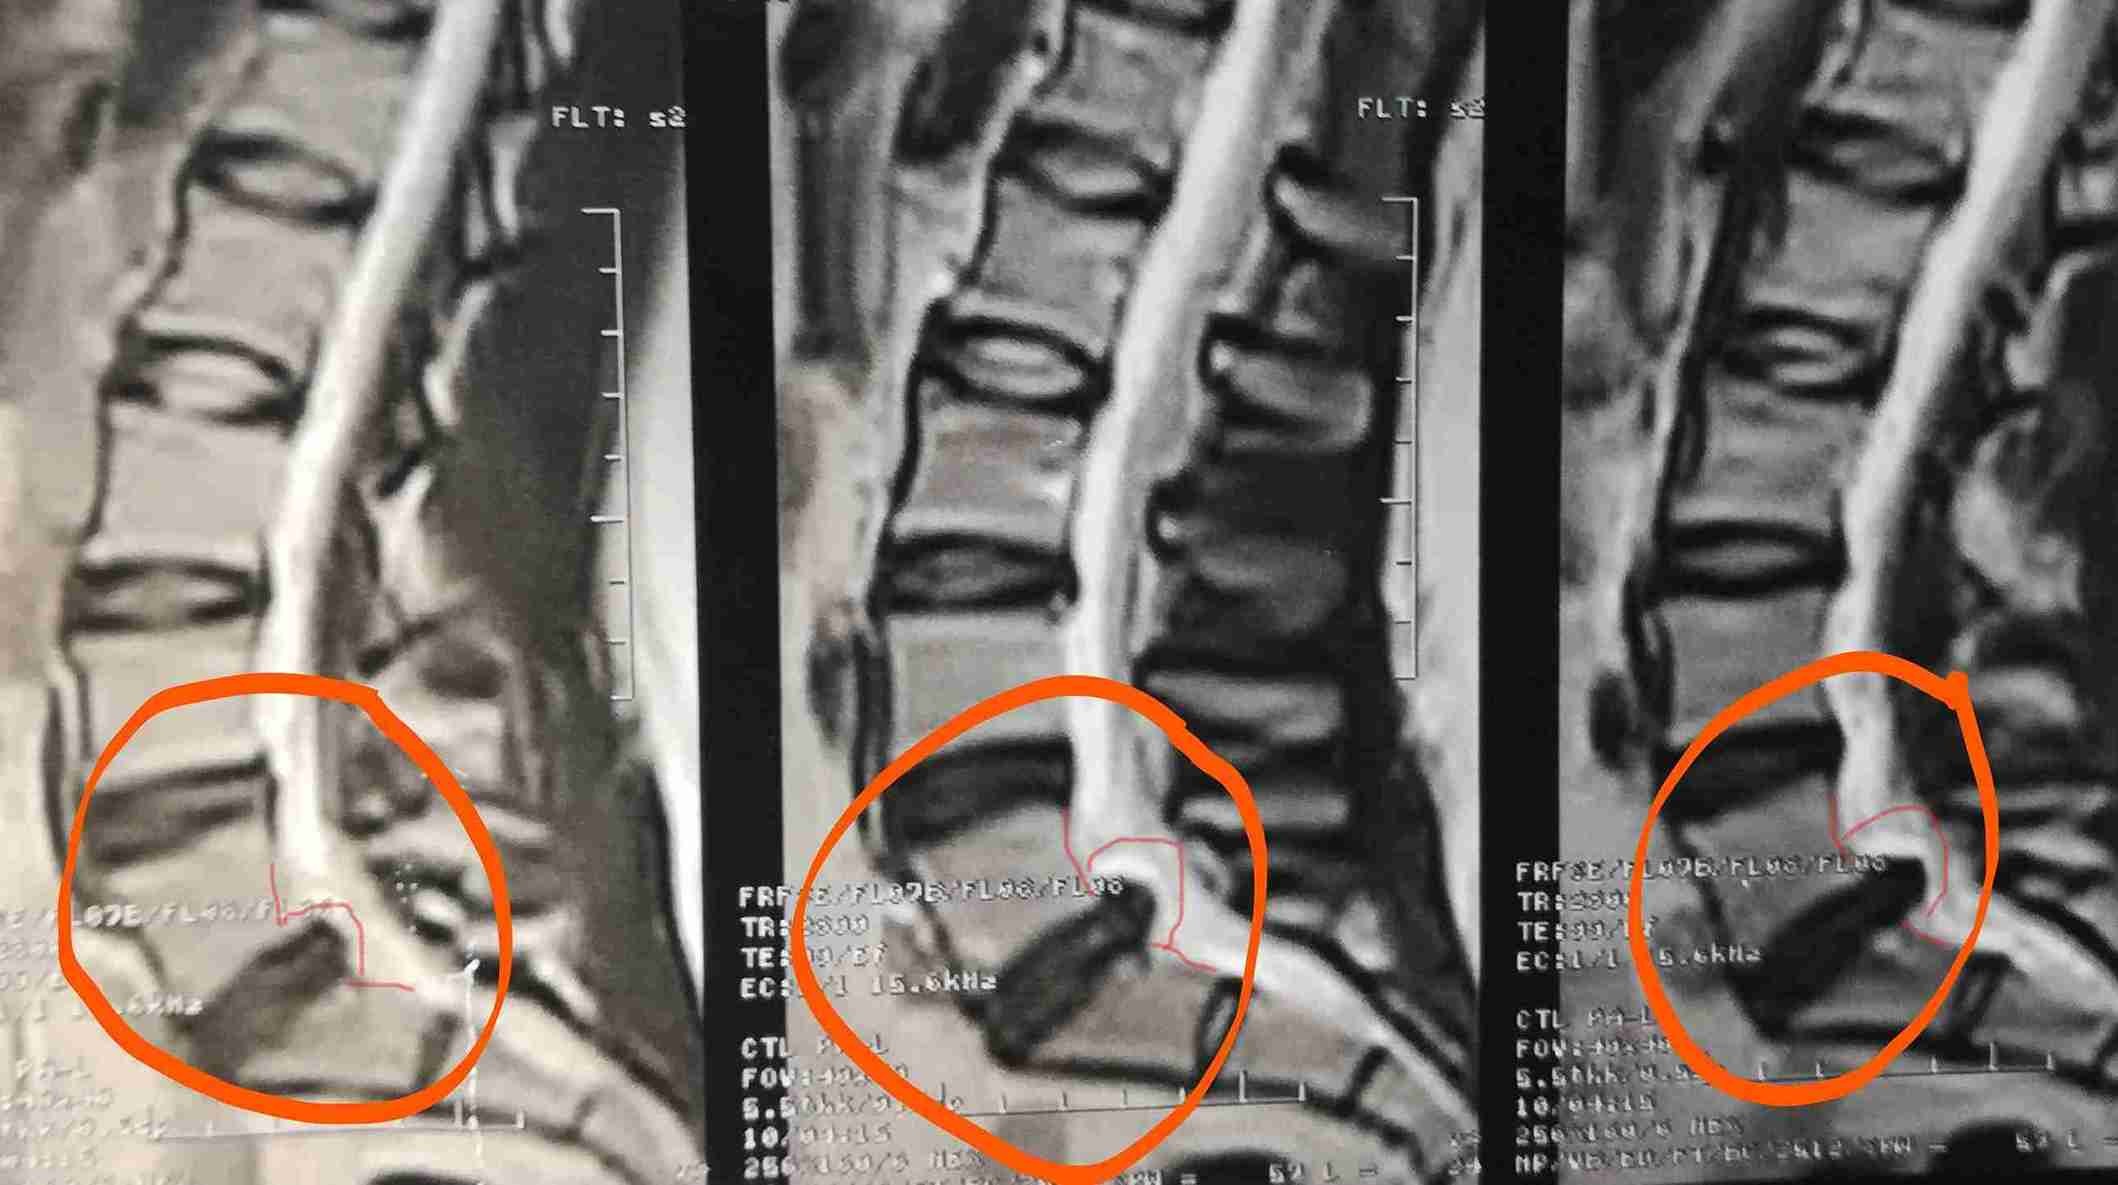

انزلاق غضروفي مع تزحزح فقاري

herniated disc with spondylolisthesis

A successful surgery was performed to treat a herniated disc accompanied by spondylolisthesis. This condition causes severe back and leg pain due to pressure on spinal nerves, significantly affecting the patient's mobility and walking ability.

• Removing herniated disc causing nerve compression

• Relieving pressure on nerve roots